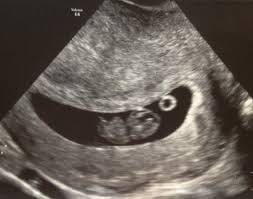

I was scared and anxious that my baby may stop growing any moment. 9 weeks pregnant and measuring small slow growth of baby. IUGR is usually diagnosed after an ultrasound shows your babys weight is below the 10 th percentile based on how many weeks pregnant you are.

Baby measuring a bit small at 28 weeks. Baby Growth Behind at 8 Weeks Ultrasound - posted in PG after IVF. If theres a heartbeat at 9 weeks the probability of a miscarriage plummets and shell have greater reassurance that her pregnancy will continue.

Most women dont find out that theyve had a late miscarriage until 12 weeks when they have. 9 weeks pregnant and measuring small slow growth of baby. Today I had my 3rd us. I was scared and anxious that my baby may stop growing any moment. For now I just want you to know that measuring small could just be that you ovulated later in your cycle than was presumed. 3 days later at 9 weeks exactly I scheduled an appointment with my RE to confirm the baby was still doing well. This type of scan is called a growth scan.